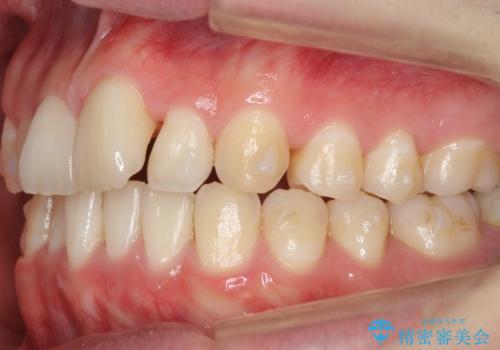

- 前歯のがたつきを主訴に来院。

左下の奥歯を後ろに移動して、中に入ってすれちがっていた小臼歯を並べました。

奥歯を後ろに移動させるために、矯正用のミニスクリューを用いました。(インプラント矯正)